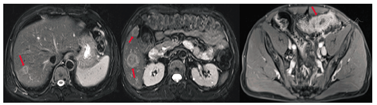

内科治疗:患者于2015年4—6月接受3周期mFOLFOX6方案(乐沙定+氟尿嘧啶+亚叶酸钙)化疗。全腹部MRI(2015年6月)提示:乙状结肠病灶段肠壁变薄,周围脂肪间隙累及加重。肝转移灶较前略缩小,盆腔多发异常信号影,不能排除转移,见图2。肿瘤标志物:CEA为68.39 μg/L,血清CA19-9 < 0.60 U/ml,CA72-4为1.09 U/ml。疗效评估:病情稳定(SD)。